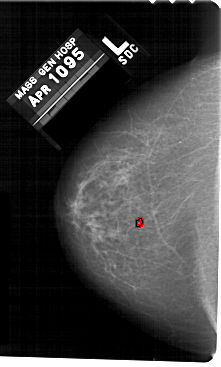

A_1479_1.LEFT_CC

LEFT_CC LINES 5491 PIXELS_PER_LINE 3301 BITS_PER_PIXEL 12 RESOLUTION 43.5 OVERLAY

FILE: A_1479_1.LEFT_CC.OVERLAY

TOTAL_ABNORMALITIES 1

ABNORMALITY 1

LESION_TYPE CALCIFICATION TYPE PLEOMORPHIC DISTRIBUTION CLUSTERED

ASSESSMENT 4

SUBTLETY 2

PATHOLOGY BENIGN

TOTAL_OUTLINES 1

BOUNDARY